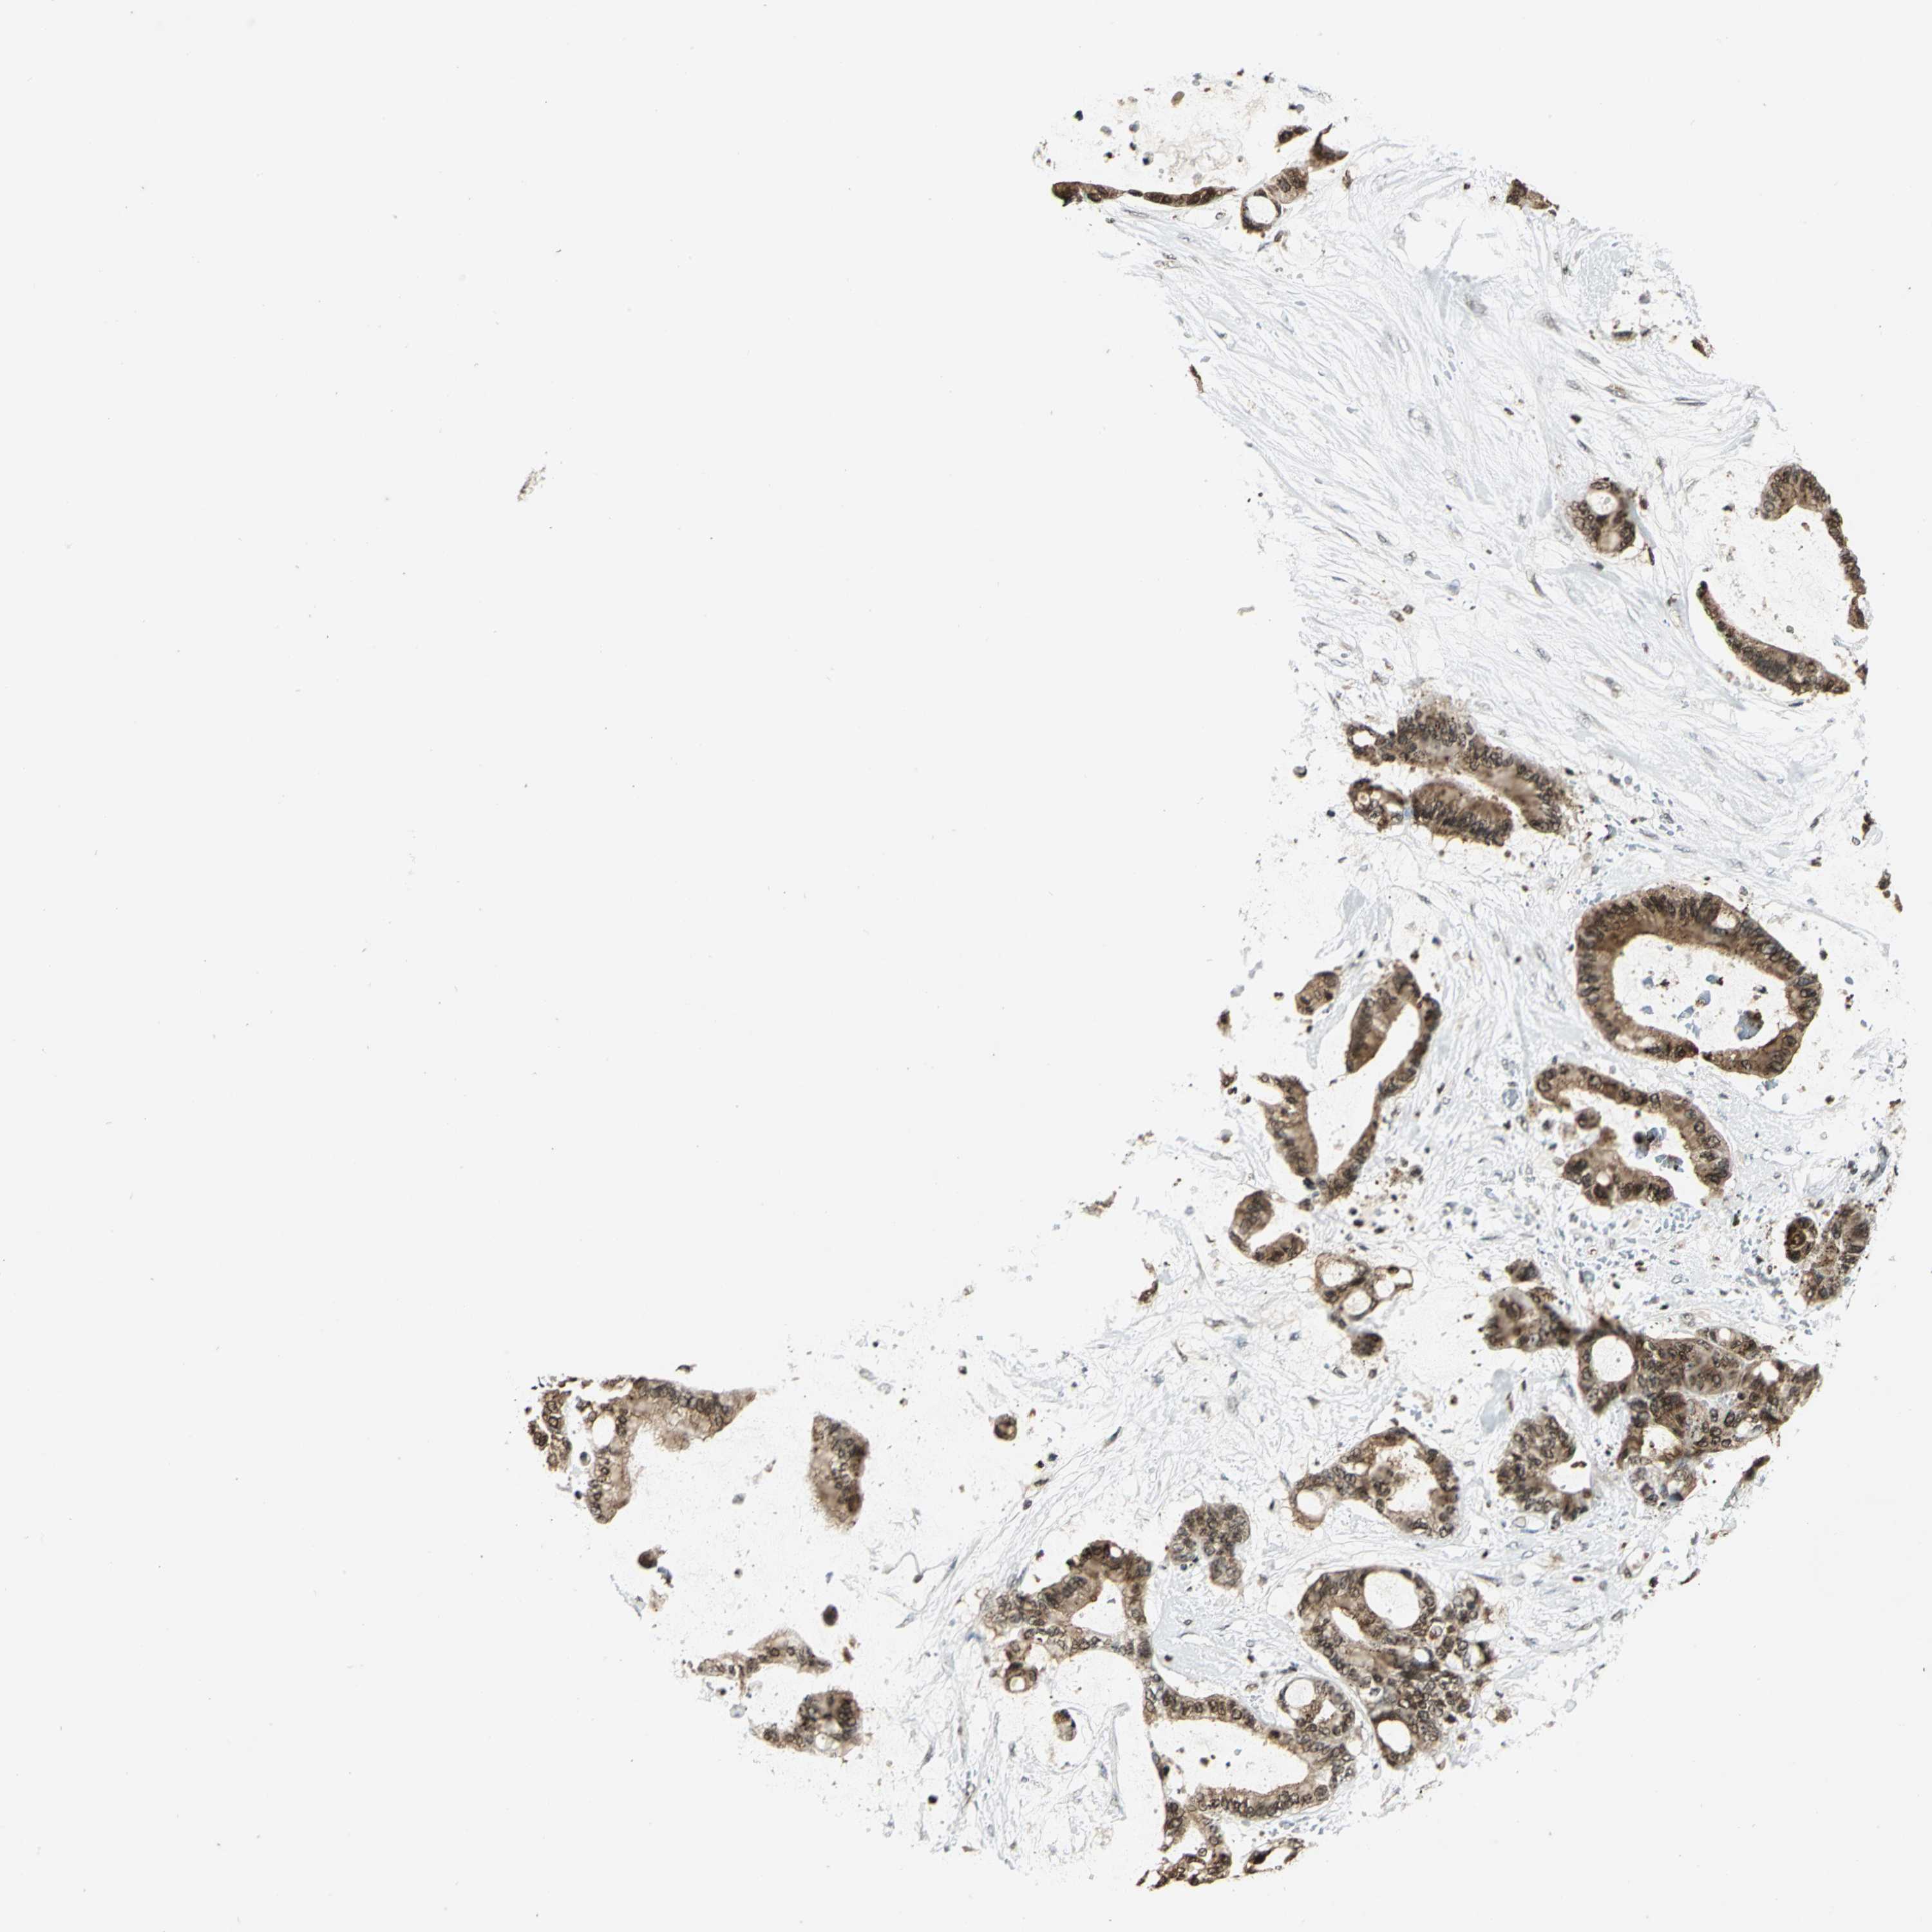

LIVER CANCER - Protein expressioni

A mouse-over function shows sample information and annotation data. Click on an image to view it in a full screen mode. Samples can be filtered based on level of antibody staining by selecting one or several of the following categories: high, medium, low and not detected. The assay and annotation is described here.

Antibody stainingi

Antibody staining in the annotated cell types in the current human tissue is reported as not detected, low, medium, or high, based on conventional immunohistochemistry profiling in selected tissues. This score is based on the combination of the staining intensity and fraction of stained cells.

Each image is clickable and will lead to virtual microscopy that enables deeper exploration of all samples and also displays staining intensity scores, fraction scores and subcellular localization as well as patient and tissue information for each sample.

Antibody HPA003162

Antibody CAB005191

Staining

High

Medium

Low

Not detected

Intensity

Strong

Moderate

Weak

Negative

Quantity

>75%

75%-25%

<25%

None

Location

Nuclear

Cytoplasmic/membranous

Cytoplasmic/membranous,nuclear

Carcinoma, Hepatocellular, NOS

Cholangiocarcinoma